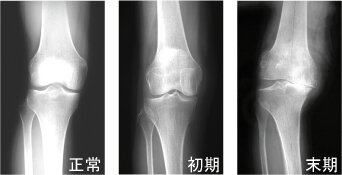

右膝

病気の進行とともに内側の関節の隙間(軟骨層)が狭くなり、やがて消失します。骨棘(こつきょく:棘のような余分な骨)も形成されてきます。そうなると正常ではまっすぐな脚が徐々にO脚に変形します。